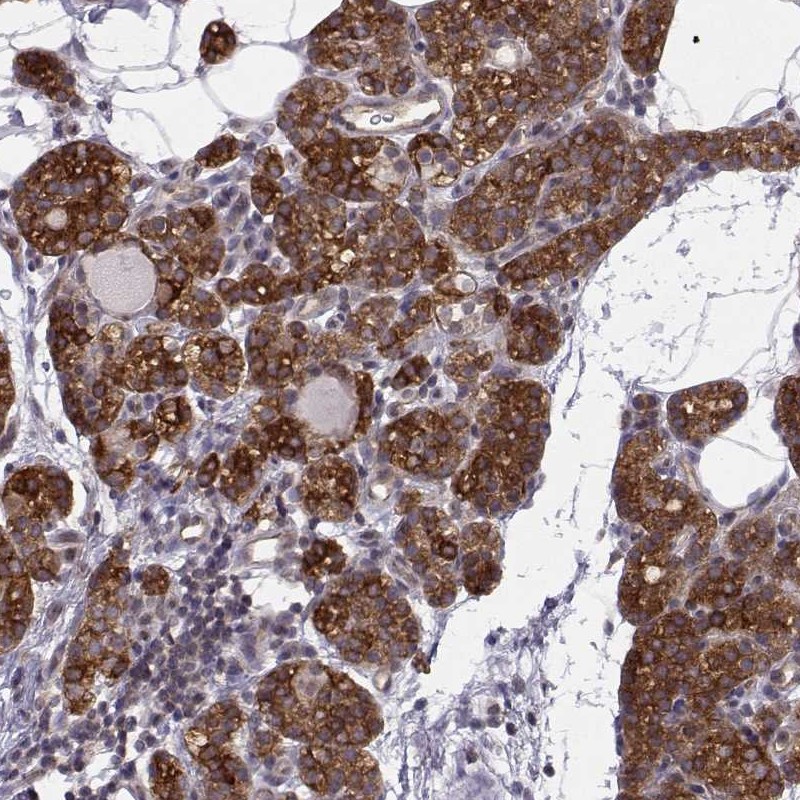

Immunohistochemistry analysis in human parathyroid gland and skeletal muscle tissues using Anti-KIF13B antibody. Corresponding KIF13B RNA-seq data are presented for the same tissues.